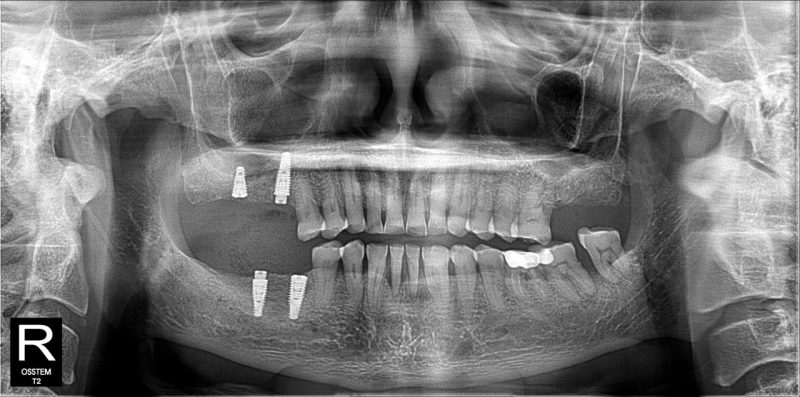

Đặt tiêu chí tối ưu, an toàn và phù hợp, đội ngũ bác sĩ chuyên môn tại SGC đưa ra giải pháp bao gồm: cấy ghép 4 trụ Implant Neodent vững chắc để khôi phục các răng hàm đã mất và bọc 24 răng sứ thẩm mỹ cao cấp.

Quá trình điều trị đã giúp chú Bé không chỉ khôi phục hoàn toàn khả năng ăn nhai, sở hữu nụ cười rạng rỡ, đều đẹp mà còn cải thiện đáng kể sức khỏe răng miệng tổng thể. Chú và vợ chú cảm thấy vô cùng hài lòng về dịch vụ cắm trụ Implant nha khoa SGC.